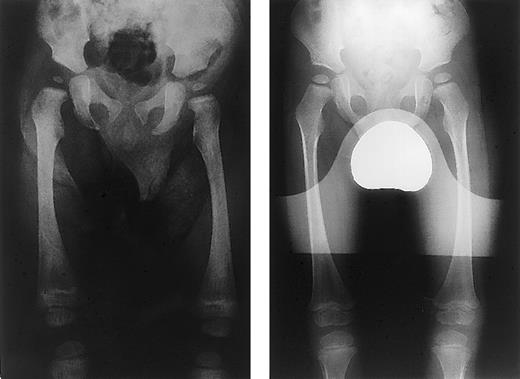

Child A is now 42 months post-BMT, and his CAII level is 3.8 U/mg Hb. He has normal bone marrow function, chimerism studies confirm full donor hematopoiesis, and his osteopetrosis has fully resolved. (Figures 1 and2). His hearing measured by conventional audiology testing is normal, although BSER measurement demonstrates minor nerve conduction abnormalities on the right side. Visual acuity is poor, and he still demonstrates abnormal VERs, but overall vision has stabilized. Interestingly, his RTA transiently improved after transplantation, as evidenced by no bicarbonate requirement for the first month. However, his acidosis subsequently recurred, and he now receives regular oral bicarbonate supplementation. He remains developmentally delayed by 18 months, which may in part be due to prolonged hospitalization post-BMT; he is now showing an encouraging response to recently introduced intensive educational support. His growth has been maintained, and height is at the 25th percentile. Brain CT at 3 years demonstrated evidence of calcification in the frontal lobes close to the junction of the white and gray matter for the first time, but repeat scanning 9 months later does not demonstrate progression of this calcification.

X-rays before and after BMT.

X-ray prior to BMT (left panel) shows diffuse sclerosis of the femora and ileum along with Erlenmeyer flask deformity (metaphyseal widening) of the distal femora. One year following BMT (right panel), x-ray shows complete resolution of sclerosis and metaphyseal widening.